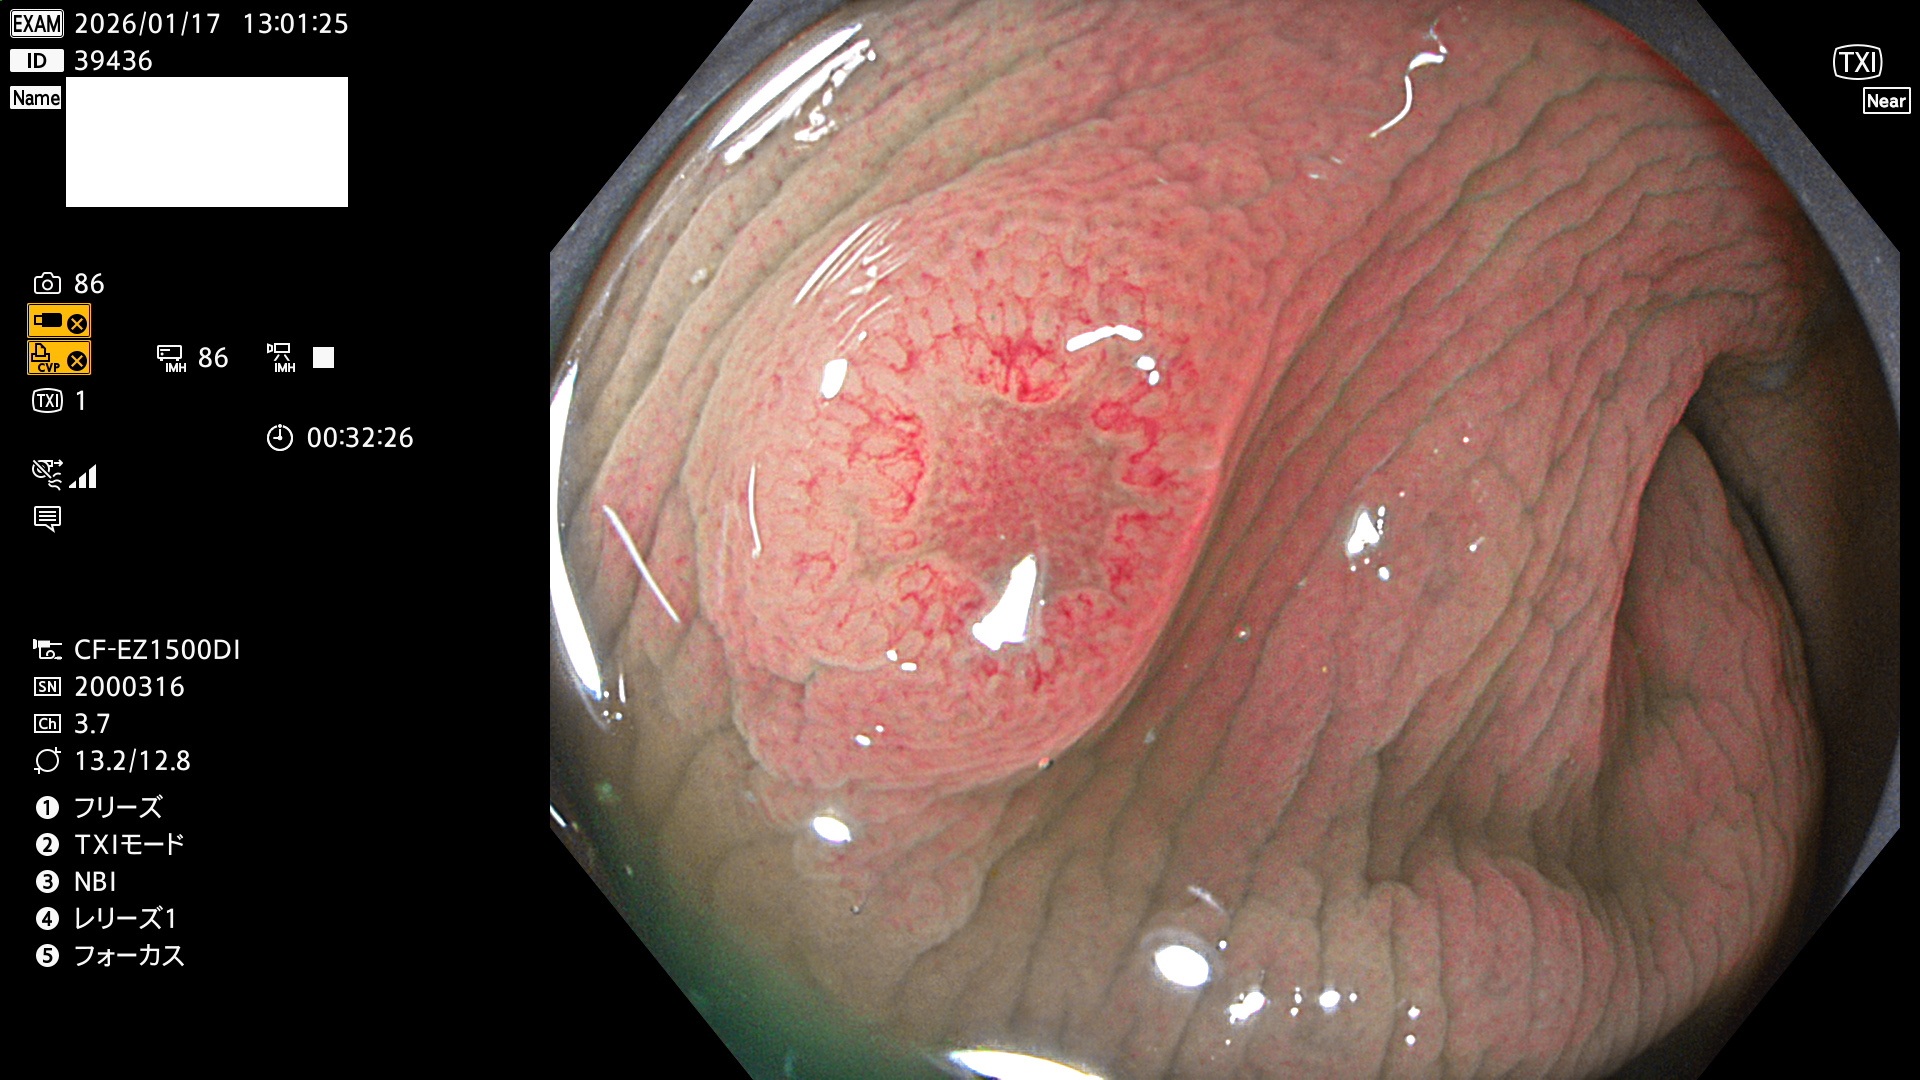

完全に平坦な物をUb、陥凹している物をUcと呼びます。Ubは認識が困難で、Ucはびらん(炎症)と紛らわしいために見落とされやすく、「内視鏡後・大腸癌」の原因になります。

専門的)Uc=De Novo癌? 内視鏡の解像度が低かった時代、このような説もありました。しかし今日の高精度内視鏡では良性の微小なUc型腺腫(APC遺伝子異常の腺腫)が日常的に見つかります。Ucこそが多段階発癌(Adenoma-Carcinoma Sequence)のMain Routeです。

毎週の検査(木・金・土・日)に発見されたUbとUc型・腺腫を、その週の日曜の夜にUPし1週間、提示します。

2026年1月15日〜1月18日の4日間(40件)で5個 (Uc_ADR=5個/40人=13%)